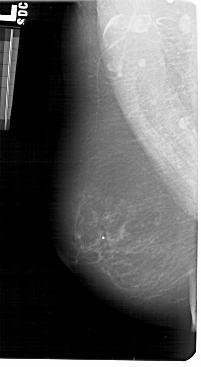

A_1428_1.LEFT_CC

LEFT_CC LINES 5431 PIXELS_PER_LINE 2581 BITS_PER_PIXEL 12 RESOLUTION 43.5 NON_OVERLAY